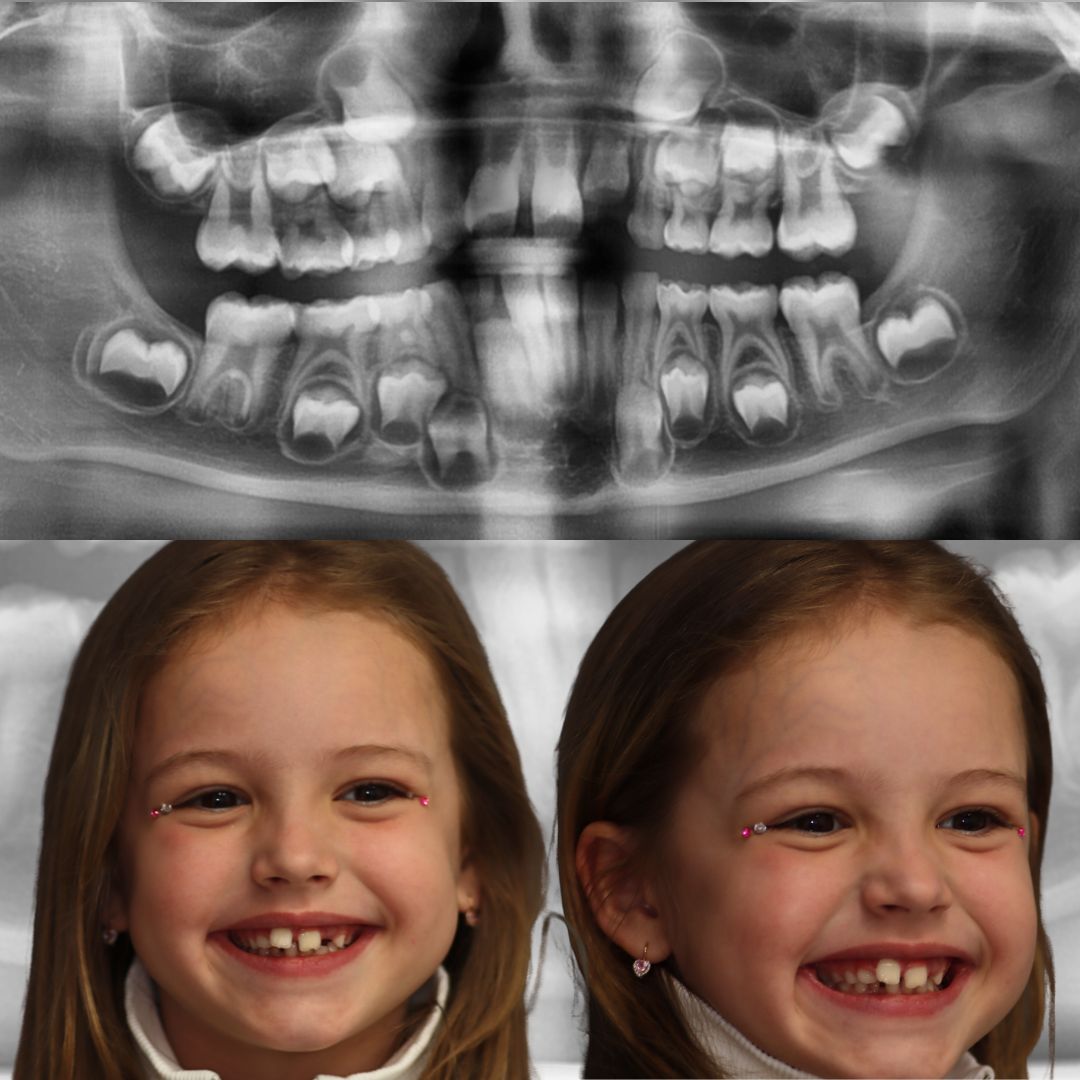

Обращение в клинику связано с жалобой на неровное положение центральных резцов, при этом проблем с прикусом не выявлено.

После диагностического обследования было предложено исправить положение зубов на детских элайнерах Kinder Smile.

Посмотрите фото ДО и ПОСЛЕ. Как вам такое 🔥 преображение?

Мастер преображения 😁 улыбки врач-ортодонт Ирина Константиновна Шевченко.